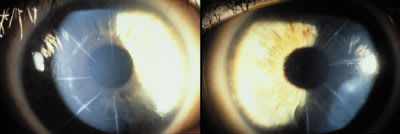

Patient VB is a 45-year-old female who underwent bilateral radial keratonomy in 1989 (Figure 1). Today her manifest refraction is OD +6.75 sph. 20/40, OS +5.50 sph. 20/40. Keratometric readings were OD 35.00 @ 46/36.00 @ 136 (+2 distortion) and OS 36.50 @ 90/36.87 @ 180 (+2 distortion) (Figure 2). The patient has made several unsuccessful attempts to wear RGP and soft lenses over the past five years and was currently wearing spectacles.

| Figure 1. Patient VB OD (left) OS (right). | Figure 2. Videokeratography OU. |